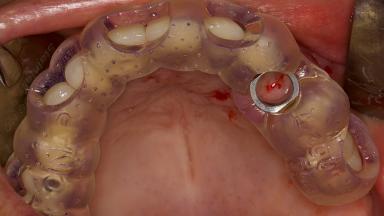

Digitally Guided Sinus Floor Elevation

In this short microlearning module on digitally guided sinus floor elevation, we delve into a specialized aspect of the digital workflow for implant-guided surgery, focusing on the use of digital guides in the sinus floor elevation technique.

- define the manufacturing process of digital guides for SFE

- explore the intraoperative use of digital guides in SFE